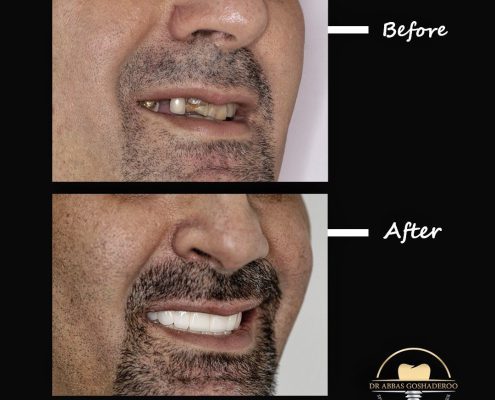

دکتر عباس گشاده رو متخصص ایمپلنت

دکتر عباس گشاده رو متخصص ایمپلنت در تهرانتلفن: 02126706197